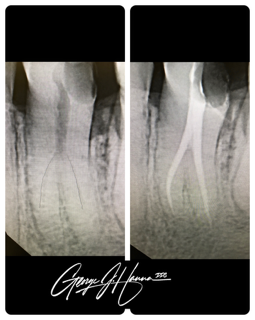

Endodontic treatments, sometimes referred to as root canals, are dental procedures used to clean out an infected root canal. Below the hard outer coating of your tooth lies a delicate tissue called “pulp.” The nerves and blood arteries in pulp provide your tooth with nutrition as it develops. When you reach maturity and your teeth are completely formed, the roots of your teeth can live without pulp and are no longer dependent upon it.

A root canal may be required to remove the pulp and any bacteria that remain when pulp becomes inflamed or infected. An untreated tooth abscess, which in turn may result in bone loss or complete tooth loss, may develop from an inflamed or infected pulp.

A root canal procedure involves numerous steps:

- To offer comfort and numb the injured region, the patient is given anesthesia

- To remove the affected tissue, a hole is cut in the tooth

- To get rid of microorganisms, the tooth canal is completely cleansed.

- To stop further infection, the canal is closed and sealed.

- To give the tooth a natural look, a crown may be applied. A tiny post may be placed into the root to support the crown in cases of severe root canal treatment.